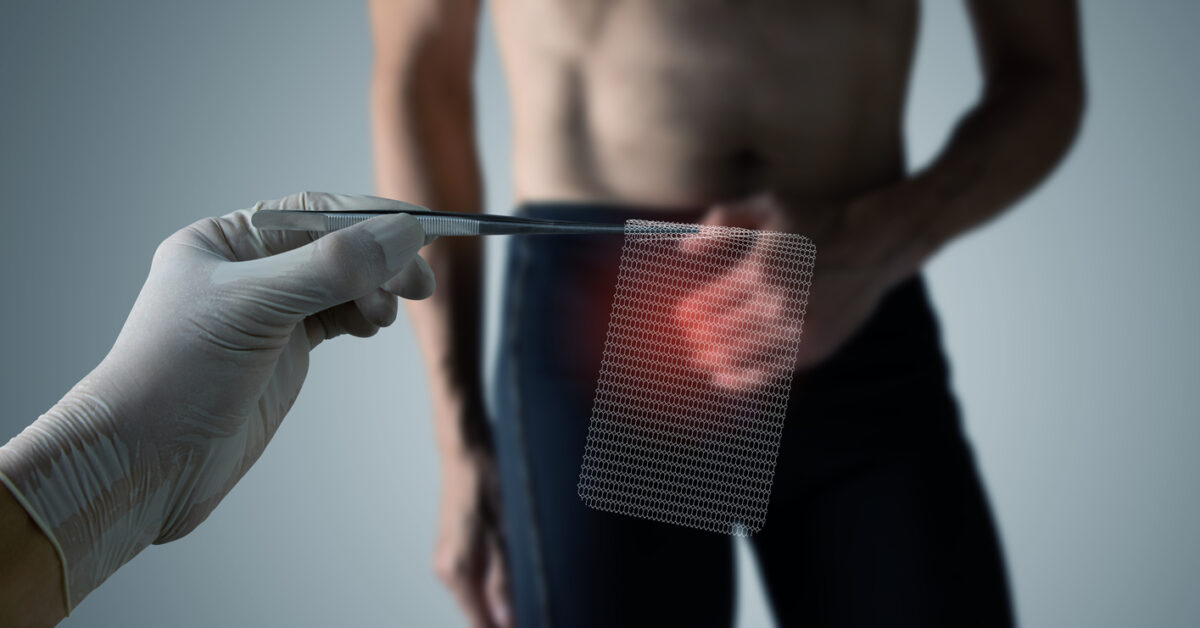

![Δημιούργησαν τεστ που το κάνεις στο σπίτι και ανιχνεύει πρώιμα σημάδια καρκίνου – Δείτε πώς γίνεται [vid]](https://www.newsit.gr/wp-content/uploads/2019/02/iStock-1011137738.jpg)